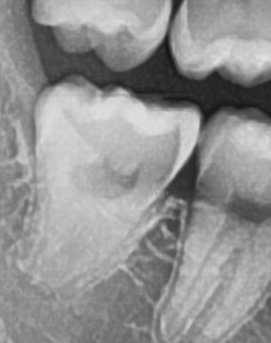

어금니 뒤 잇몸 부음의 문제는 사랑니가 원인이 되는 경우도 많은데 사랑니는 특히 현대인들의 경우 제대로 나오지 못하고 매복되는 경우가 많으며 완전히 나오지 않은 사랑니는 잇몸 속에서 자라면서 주변 잇몸을 자극할 수 있고, 일부만 노출되면 음식물이 끼면서 염증이 생기기도 하며 특히 어금니 뒤쪽 잇몸이 붓고 지속적으로 불편함을 느낀다면 사랑니로 인한 염증을 의심해 볼 수 있어요. 사랑니로 인한 문제의 경우 단순한 소염제나 구강 세정제로 해결되지 않고, 사랑니를 발치해야 잇몸 염증이 해결되는 경우가 많이 있어요

결론적으로는 통증이 심하거나 염증이 오래 지속되는 경우에는 치과를 방문해서 정확한 진단을 받는 것이 중요한데 단순한 잇몸 염증이라면 치석 제거와 항생제 치료로 호전될 수 있지만, 치주염이 진행된 경우라면 보다 적극적인 치료가 필요할 수 있어요. 만약 사랑니로 인해 잇몸이 자꾸 붓는다면 사랑니 발치를 고려해야 하겠고 사랑니가 완전히 매복되어 있다면 수술적인 방법으로 제거해야 할 수도 있어요. 특히 반복적으로 붓는다면 사랑니 검사를 받아보거나, 치과에서 정밀 검진을 통해 치주 상태를 확인하는 것이 필요하다는 점에서 어금니 근처의 잇몸이 반복적으로 불편하다면 꼭 치과를 찾아보시길 바라고 있어요